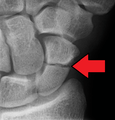

A subtle scaphoid fracture